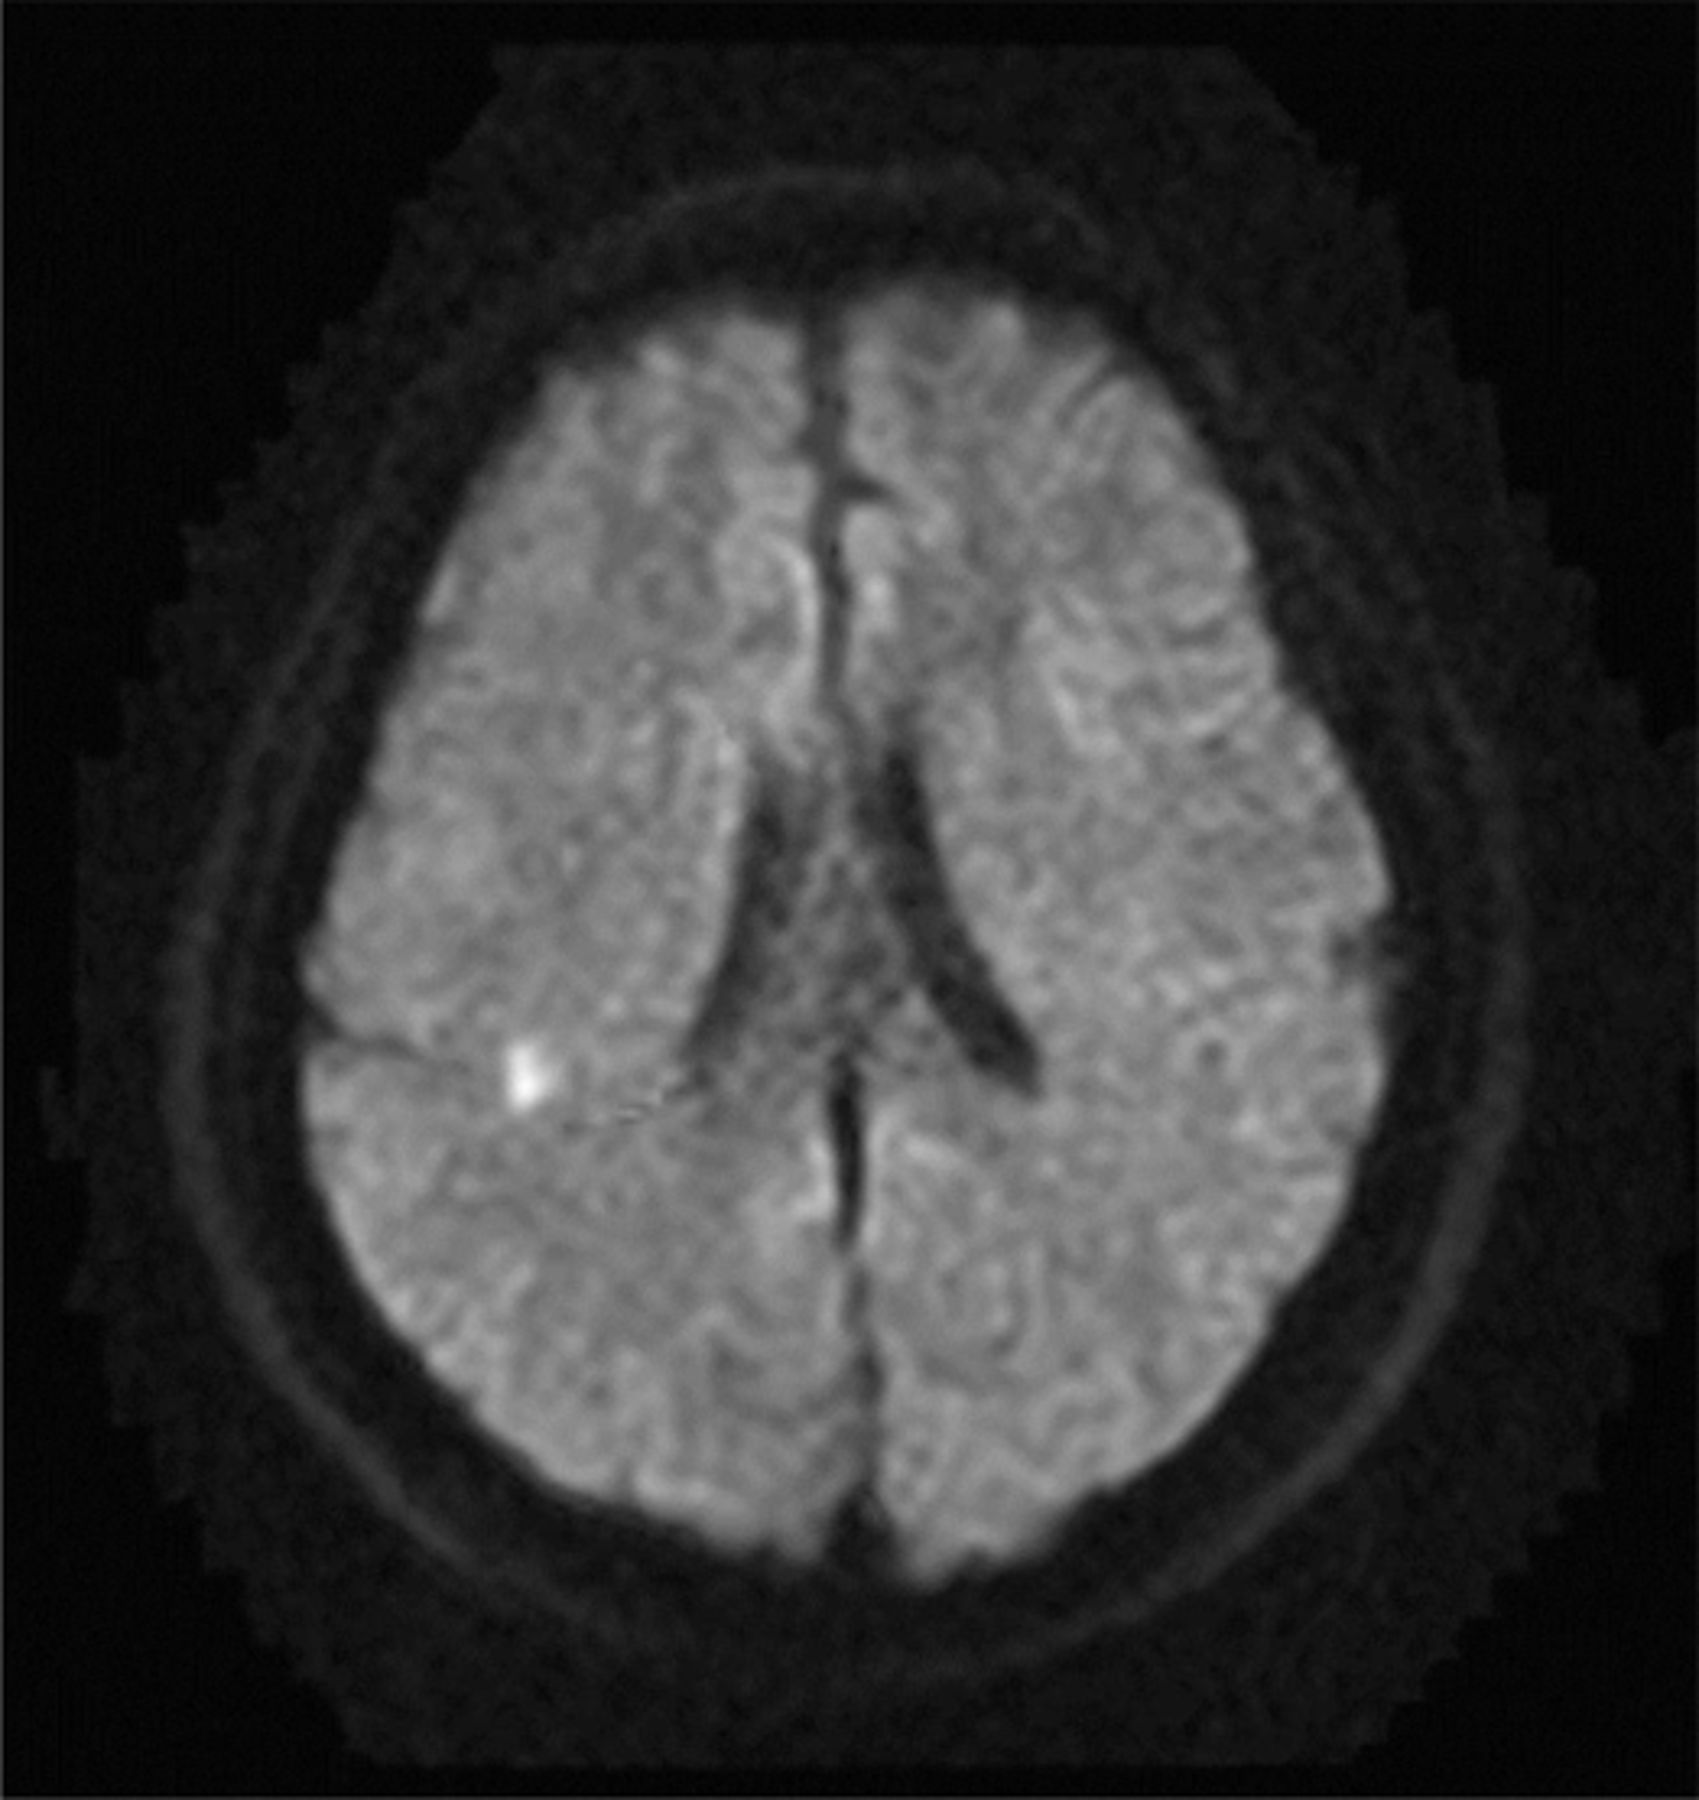

一个60岁的老男人有心房颤动病史的急性发作的弹道运动的肢体与感官灭绝(视频首页神经病学®网站www.首页neurology.org)。病人接受利培酮和抗凝剂;症状消退后3天。脑部核磁共振成像显示急性梗死的权利后顶叶(图1)和SPECT显示低灌注的frontoparietal区域(图2)。